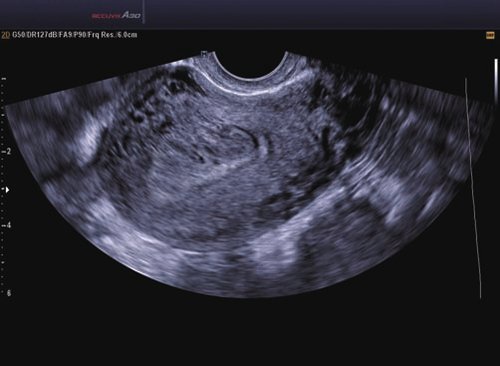

15 EC4-9IS Endokavitär 4-9 Frauenheilkunde und Geburtshilfe, Endovaginal, Fetal, Urologie

16 VR5-9 Endokavitär 5-9 Frauenheilkunde und Geburtshilfe, Urologie

Das Samsung Accuvix A30 ist ein hochwertiges Ultraschallsystem, das mit seiner 3D-Technologie herausragende Ergebnisse ermöglicht. Das Sonographiegerät besitzt 5 Sondenanschlüsse und ist mit 20 unterschiedlichen Schallköpfen kompatibel. Mit dem A30 können Schallköpfe vom Typ Konvex, Mikrokonvex, 3D-Konvex, CW, Phased Array, Linear und Endokavitär verwendet werden. Bei zwei der Sonden handelt es sich um S-VUE Ultraschallsonden, die durch ihre höhere Bandbreite noch feinere Scans erzeugen.

Das Ultraschallsystem hebt sich besonders durch seine 3D-Technologie wie die Face Auto Detection für detaillierte Ultraschallbilder von Föten oder das Volume Shade Imaging, das sich auf die lebensnahe Darstellung von Schattierungen und Hauttönen fokussiert, ab. Mit weiteren wertvollen Technologien wie dem ElastoScan™ werden Tumore schneller erfasst und durch die HD Volumen Bildgebung sowie das DMR+™ eine erstklassige Bildqualität erzielt.